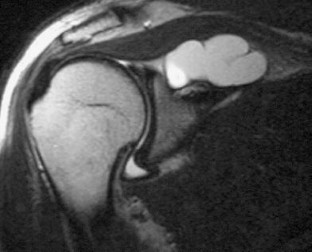

Fig. 2